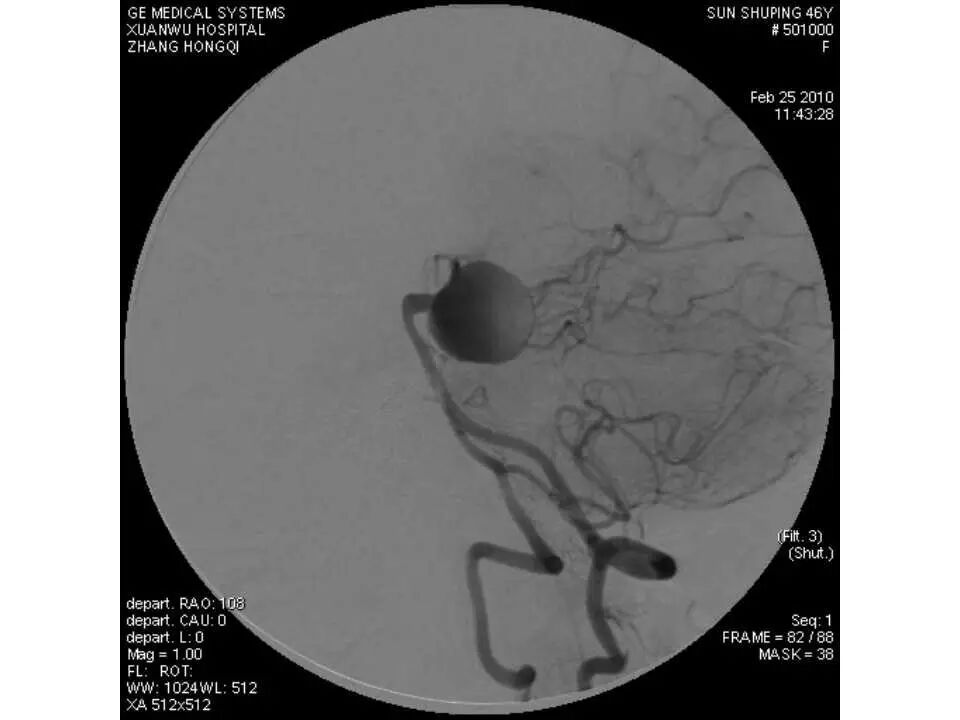

今天为大家分享的是“强生医疗CNV-神经介入专栏”第十五期,由首都医科大学宣武医院何川教授带来的“颅内动脉瘤介入治疗”精彩讲课视频及PPT,欢迎观看、阅读。文章仅代表作者个人观点,如有不同见解,欢迎同道斧正!

何川 ,首都医科大学宣武医院副主任医师,中国医师协会神经介入专业委员会常务委员,长期从事脑血管病和脊髓血管病的手术及介入治疗和相关研究工作。首都医科大学神经外科博士,师从于中国神经介入开创人凌锋教授;日本东北大学医院脑血管病治疗科博士后,师从于日本国脑血管病血管内治疗的开创者高桥教授。